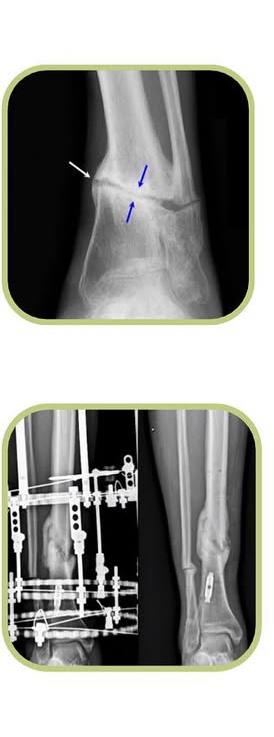

Ocorre devido à ausência de consolidação de uma fratura no período esperado sendo uma condição que pode ser bem desafiadora para o paciente e ortopedista. Dentre as causas temos a infecção óssea, lesão de pele e músculos, falha de síntese, perda ou falhas ósseas além das comorbidades do paciente. Quanto ao tratamento temos como opções a realização da mudança de síntese, transporte ósseo, enxertos ósseos sintéticos ou biológicos e antibioticoterapia se infecção associada. Se você tem interesse em saber mais, agende uma consulta comigo.